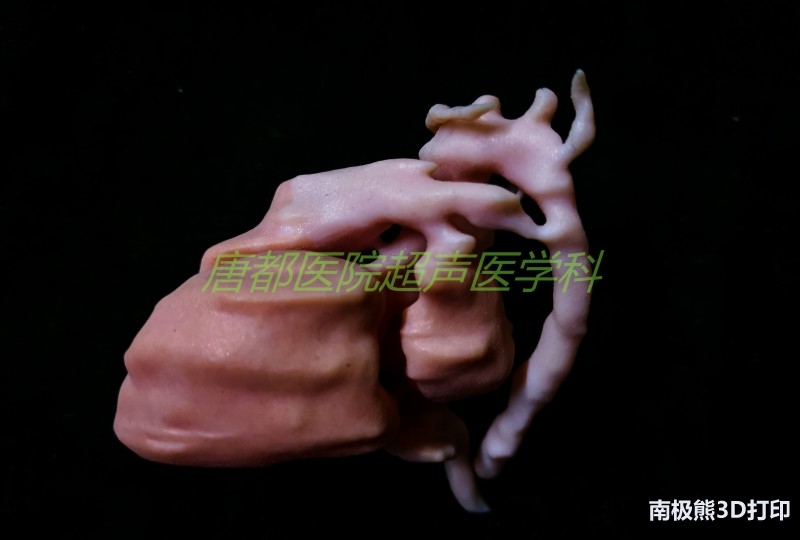

近日,空军军医大学唐都医院超声医学科3D打印研究中心完成了基于超声影像数据的胎儿心脏多色3D打印。该模型完整地呈现了包括胎儿心脏四腔、主动脉弓、降主动脉、动脉导管、肺动脉、上腔静脉、下腔静脉、无名静脉以及卵圆孔、气管和左右主支气管等解剖结构,成功地将胎儿心脏及其周围大动脉、静脉和气管之间的空间结构关系精准还原,最终利用光固化多色打印技术清晰地展现出来。

胎儿心脏模型整体体积相比于实际大小放大了8倍,模型的长宽高分别约为33 mm、25 mm和24 mm。此次三维建模历时3小时,色彩贴图6小时,3D打印及后处理约8-9小时完成。

该技术的难点在于建模时对超声图像的识别和把握,必须将胎儿心脏与周围的大血管和气管等结构准确地三维重建。通过三维重建,能够将解剖结构实体化,更清晰直观地展现异常的解剖结构以及它们之间的空间位置关系。通过实体模型,医生能够更加直接地进行病情的讨论和治疗方案的设计,必要时还可以利用模型进行手术模拟,大大提高工作效率。